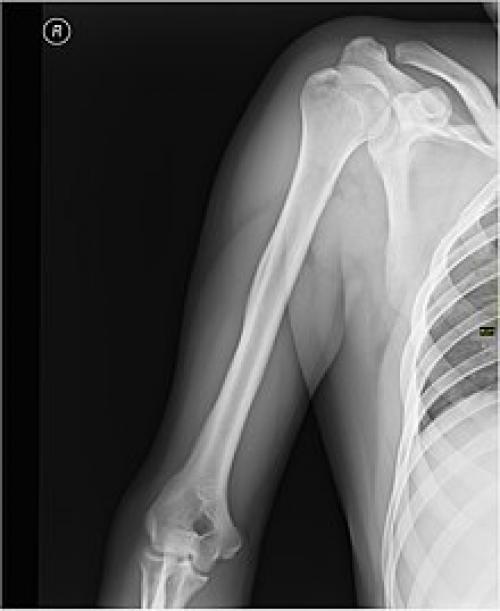

Плечо (часть тела)

В обычном, не анатомическом словоупотреблении под плечом понимается не «верхняя часть руки», а часть туловища от шеи до руки. Анатомически эта часть соответствует плечевому суставу и надплечью , то есть — поясу верхних конечностей .

Каркасом плеча служит плечевая кость .

При травмах плеча возможно повреждение нервов и сосудов, а также переломы плечевой кости, наиболее частой локализацией которых является шейка плечевой кости.